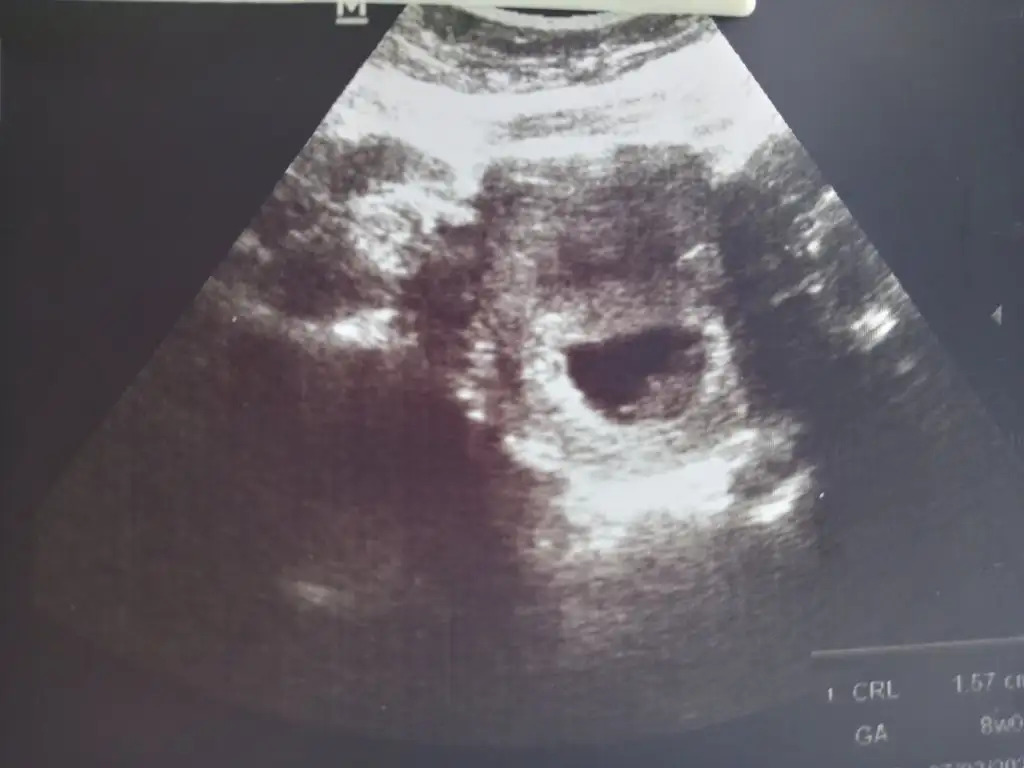

Gözün aydın canım benim çok sevindimKızçeler geldiiim doktordan kalp hareketleri başlamış ama dinletmiyim bebeğe zarar şuan çok küçük dedi, progestana başlattı, dikkat etmeye devam et dediiGüzel haberler aldım çok şükür

Ne güzel maşallah, sağlıkla kucağına almayı nasip etsin inşallah RabbimNormalde 3-4 temmuz gibi adet olmam gerekiyordu ben kimyasala bağlı gecikebilecegini düşündüm ama hafif pembemsi bir akıntı görünce test yaptım gecikmenin dördüncü günü o zaman kanda çıktı gebelik. Bir hafta sonra 15 temmuzda keseyi gördük işte bugün de kalp atışını duydum çok şükür![]()

Maşallah onaMerhabaa bugün doktora gittim miniğimin kalbini de duydum kendini de gördüm çok şükür